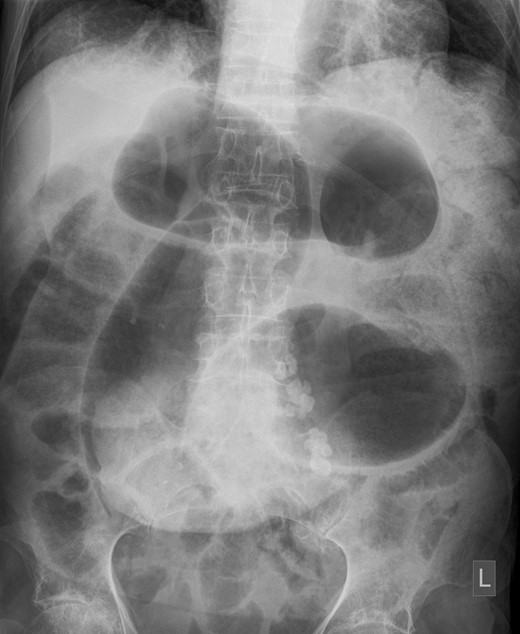

Mr. X had a plain film abdominal x-ray taken in ED which displayed dilated loops of bowel, Fig. 2. CT abdomen and pelvis was performed which showed an abrupt transition point in the sigmoid colon and a twisting of the sigmoid colon consistent with a volvulus, Fig. 3.

Plain film abdominal X-ray taken on admission. Note coffee bean sign in Left iliac fossa.